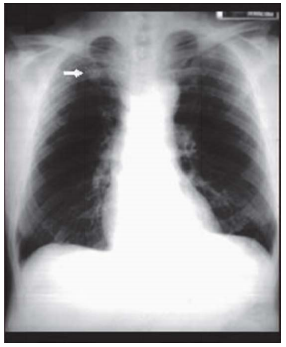

Homem com 35 anos de idade procura a

Unidade Básica de Saúde devido a uma

alteração identificada nos exames

admissionais, reproduzida na radiografia de

tórax seguinte. Refere tosse seca há 40 dias, constante, diária, nunca tratada. Nega febre,

dispneia, hemoptise e perda de peso. É

fumante, com uma carga tabágica de 20

anos.maço. O exame físico é normal. A

conduta mais apropriada para este paciente,

neste momento, é: